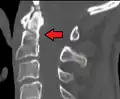

Fractures of the dens, not to be confused with Hangman's fractures, are classified into three categories according to the Anderson Alonso system:

- Type I fracture - Extends through the tip of the dens. This type is usually stable.

- Type II fracture - Extends through the base of the dens. It is the most commonly encountered fracture for this region of the axis. This type is unstable and has a high rate of non-union.

- Type III fracture - Extends through the vertebral body of the axis. This type can be stable or unstable and may require surgery.

Type 3 odontoid fracture

Type 2 dens fracture